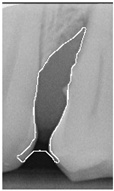

To ensure that only the area framing the symptom is preserved, and to remove the rest of the interfering areas or lines, the symptom frames are extracted according to the closure algorithm, i.e., the maximum connectivity area can be preserved to remove the frames of the non-symptomatic areas, as shown in Figure 7b. After the closure process, some of the frame lines are less smooth than others, which may affect the discrimination accuracy. To deal with this situation, this study performs the filling of the frame lines at the symptom area to facilitate the training of the model. Black and white are chosen to highlight the contrast and to compare the difference in discrimination between the two fill colors, as shown in Figure 7c,d.

Figure 7. Comparison of extracting the closed area and filling. (a) Close operation. (b) Extracting the closed area. (c) Filling with white. (d) Filling with black.